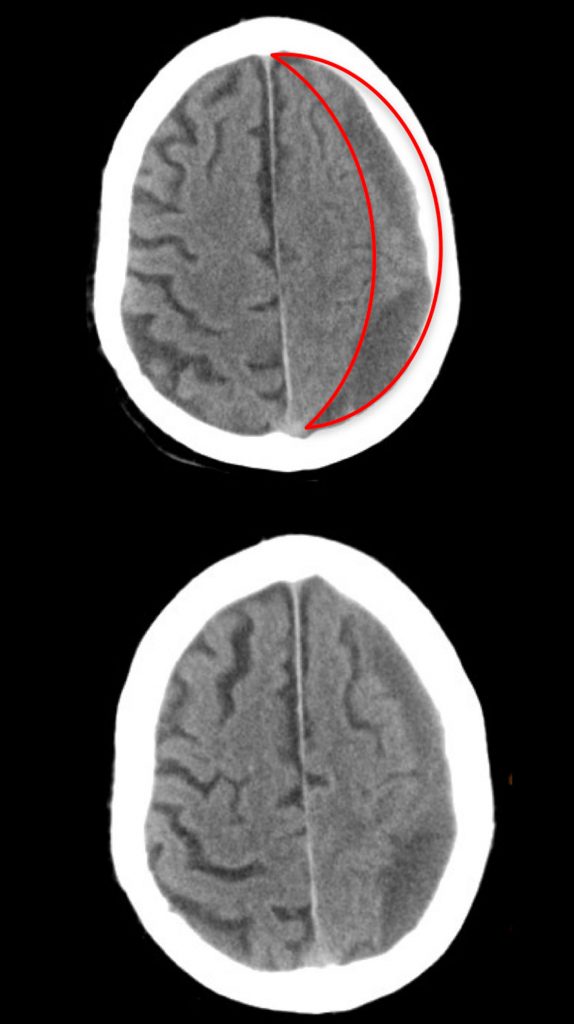

Diagnóstico: Hematoma subdural hemisférico Izquierdo.

Tipo de Cirugía: Drenaje de Hematoma Subdural

Fecha de la cirugía: Septiembre 21 del 2018

Tuvimos la fortuna de llegar con el Dr. Rodrigo Lorenzana, necesitábamos un Neurocirujano, porque mi papá de 88 años (hoy 89, 90 en noviembre) tenía un hematoma subdural que había que operar. Llegamos a la clínica Londres por el seguro de gastos médicos de mi papá. El médico asignado fue Rodrigo Lorenzana. Un médico que en todo momento fue muy paciente , muy amable y empático con el. Siempre explicando a mi papá y a la familia todo lo que venía por delante.

Mi papá desde que lo conoció se sintió seguro y confiado con el doctor. Nos dio mucha confianza demostrándonos total seguridad de la operación que realizaría. Cuando lo operó nos tuvo informados en todo momento. Lo cuidó mucho, entre la edad y un infarto que tuvo mi papá hace años, pues ya sabrán lo preocupados…

La operación fue un éxito, mi papá salió perfecto y se recuperó por completo. Siempre vigilado y cuidado por el Dr. Lorenzana.

Hoy a 11 meses de la operación, mi papá esta perfecto, con un segundo aire maravilloso. Por cierto, mi papá y el Doctor Lorenzana tienen una cita pendiente…ir a un partido de los PUMAS…